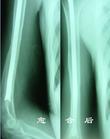

骨折固定術 1.四肢閉合性骨折者(包括關節內和近關節骨折經手法整復成功者)。對股骨骨折,因大腿部肌肉收縮力強,常須配合皮膚牽引或骨牽引。

2.四肢開放性骨折,創面小或經處理創口已閉合者。

禁忌證1.較嚴重的開放性骨折及傷口感染嚴重者。

2.難以整復的關節內骨折。